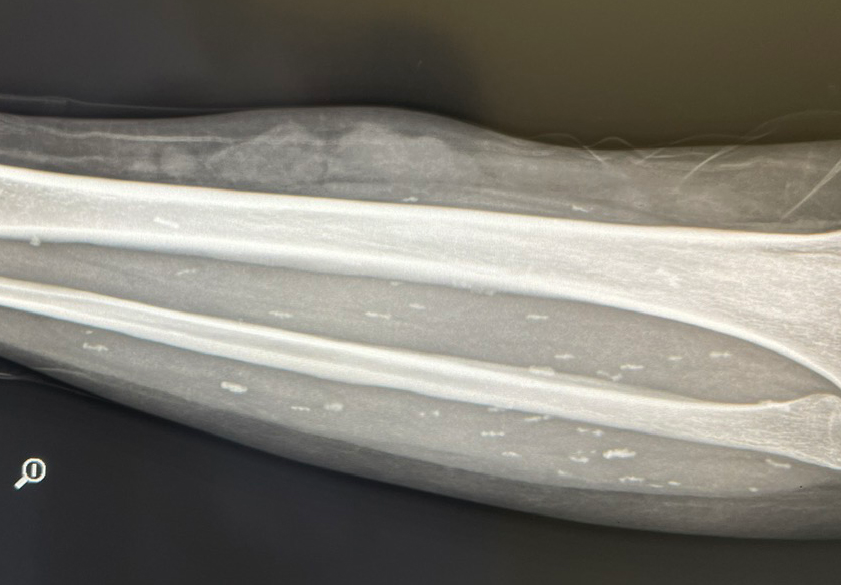

Image of the worm residing in the patient's leg through X-ray. Photo: BSCC.

Mr. N. experienced lower back pain spreading to his right side and had painful urination. At Thanh Son Medical Center (Phu Tho), an abdominal CT scan revealed dilated right renal pelvis and ureter due to middle 1/3 ureteral stones, bilateral kidney stones, gallbladder stones, and a right inguinal hernia. Most alarmingly, tapeworm larvae, 3-5mm in diameter, were found scattered throughout his body.